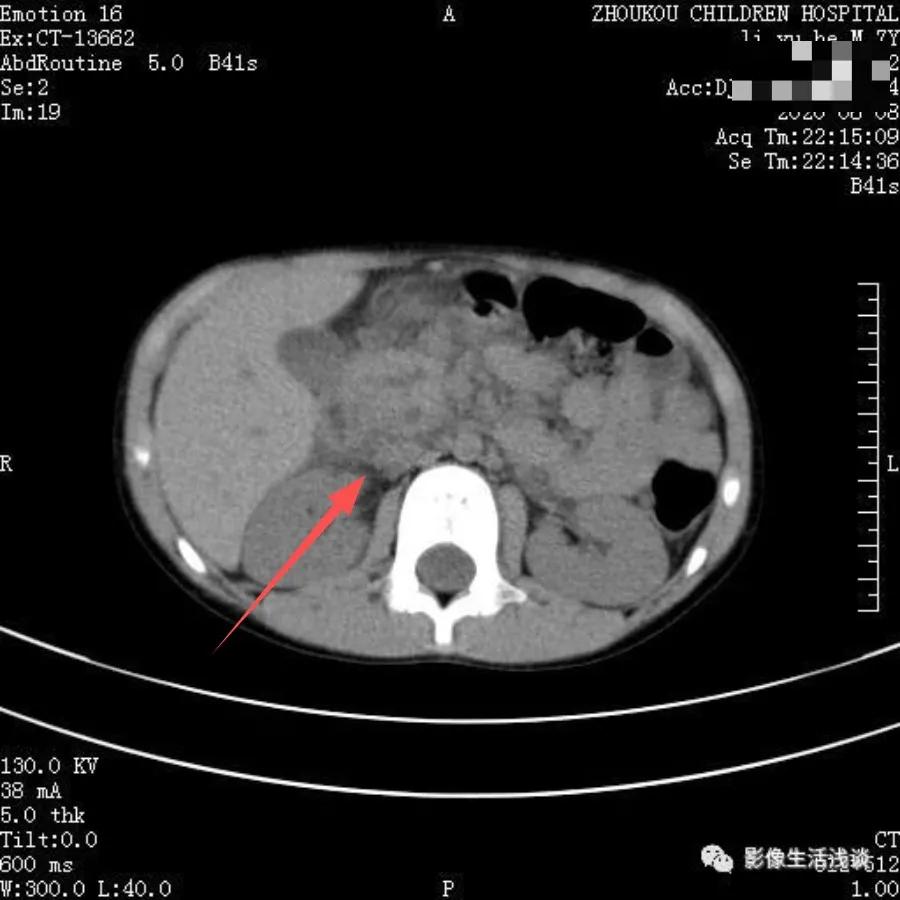

一般回肠-结肠型多见,多数患儿在不超过24小时的情况下,行透视下动态观察空气灌肠复位成功率高,小肠套叠如果套叠比较长,多数需要手术复位。下面是一例在外院以肠梗阻病人收入我院,在CT下我们可以明显看到小肠内见明显同心圆征象,肠壁局部明显增厚,肠管内见多发大小不等液气平面影,考虑小肠套叠伴高位肠梗阻,术后证实回肠-回肠-结肠套叠。